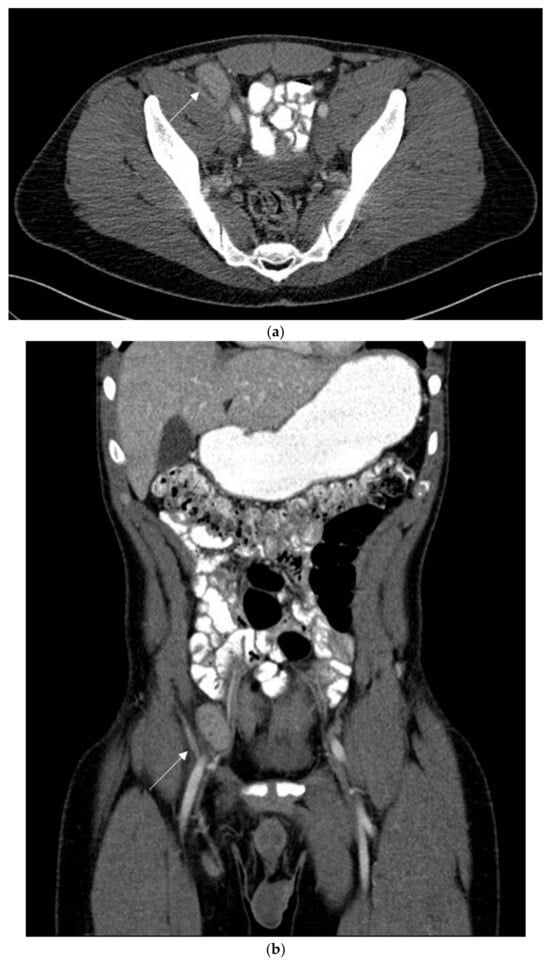

2. Case Report